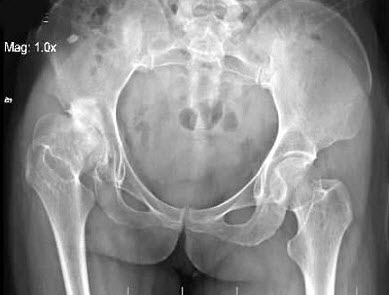

右髋关节疼痛,跛行1年多,无明显外伤史,双髋关节摄片如图,最可能的诊断是( )

A、右髋关节退行性关节病

B、右髋关节创伤性关节病

C、右髋关节结核

D、右髋关节化脓性关节炎

E、右髋关节神经性关节炎